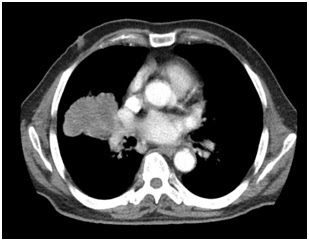

11. Bilgisayarlı

Toraks Tomografi kesiti altta verilen hastada diyafram patolojisi ne olabilir?

a)

Bochdalek

hernisi

b)

Morgagni

c)

Sliding

herni

d)

Paraözofageal

e)

Mikst